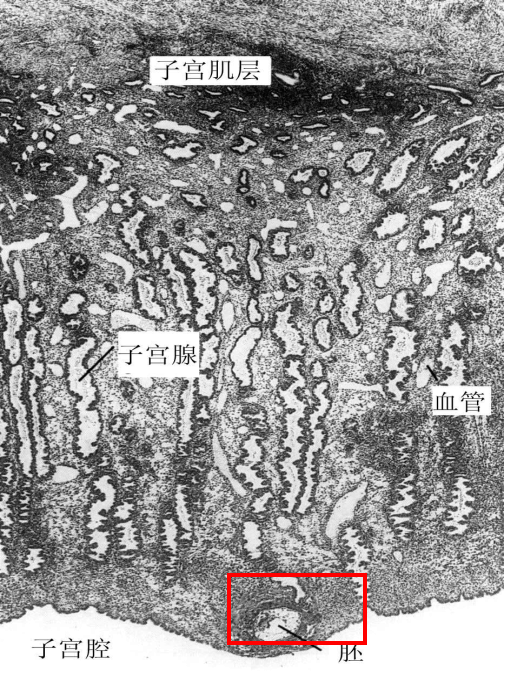

胚泡植入子宫内膜光镜图

包埋在子宫蜕膜中的胚(约4周龄)

植入过程滋养层的变化

植入过程中,与内膜接触的滋养层迅速增生,形成内、外两层细胞。(合体滋养层、细胞滋养层)